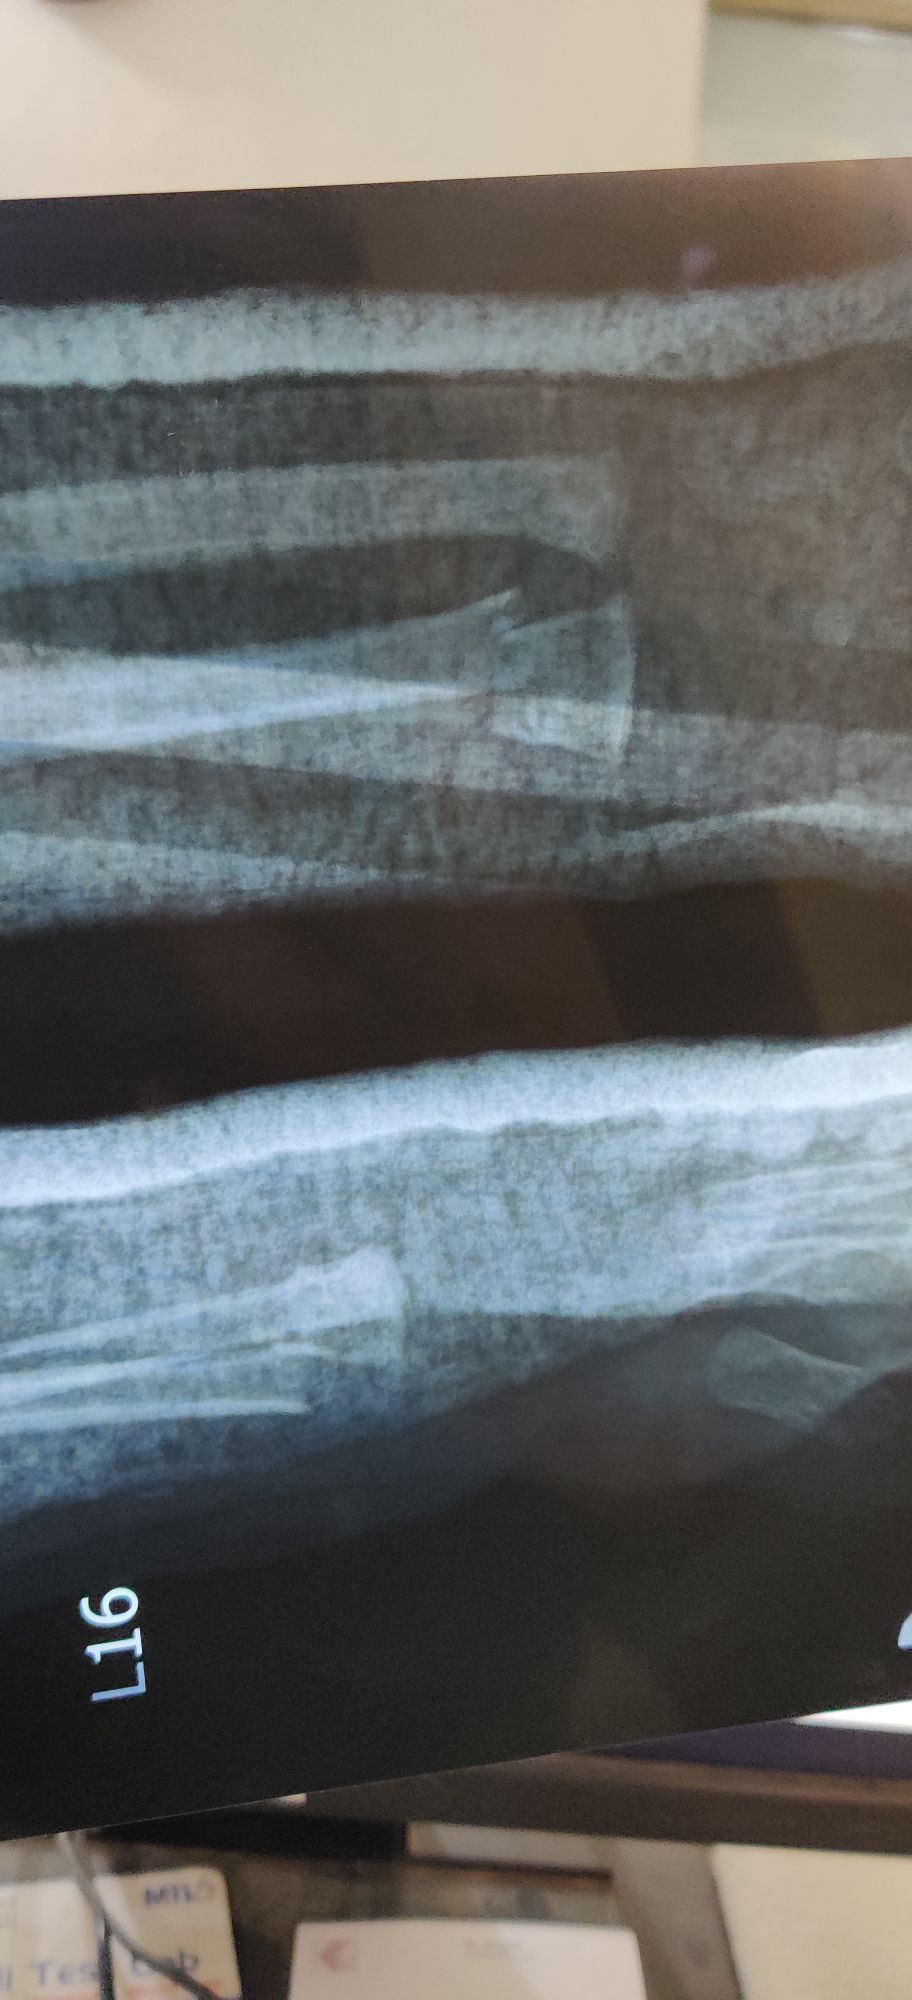

Distal end of Radius Fracture

Orthopaedics

Fracture

Radius